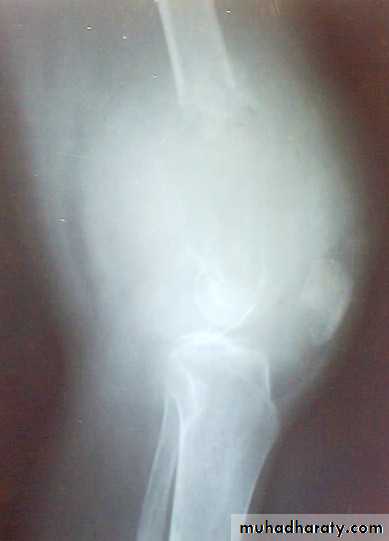

X-ray show eccentric osteolytic lesion in the end of long bone ,subchondral, trabeculated (soap bubble appearance). The cortex is thin, expanded or even perforated.